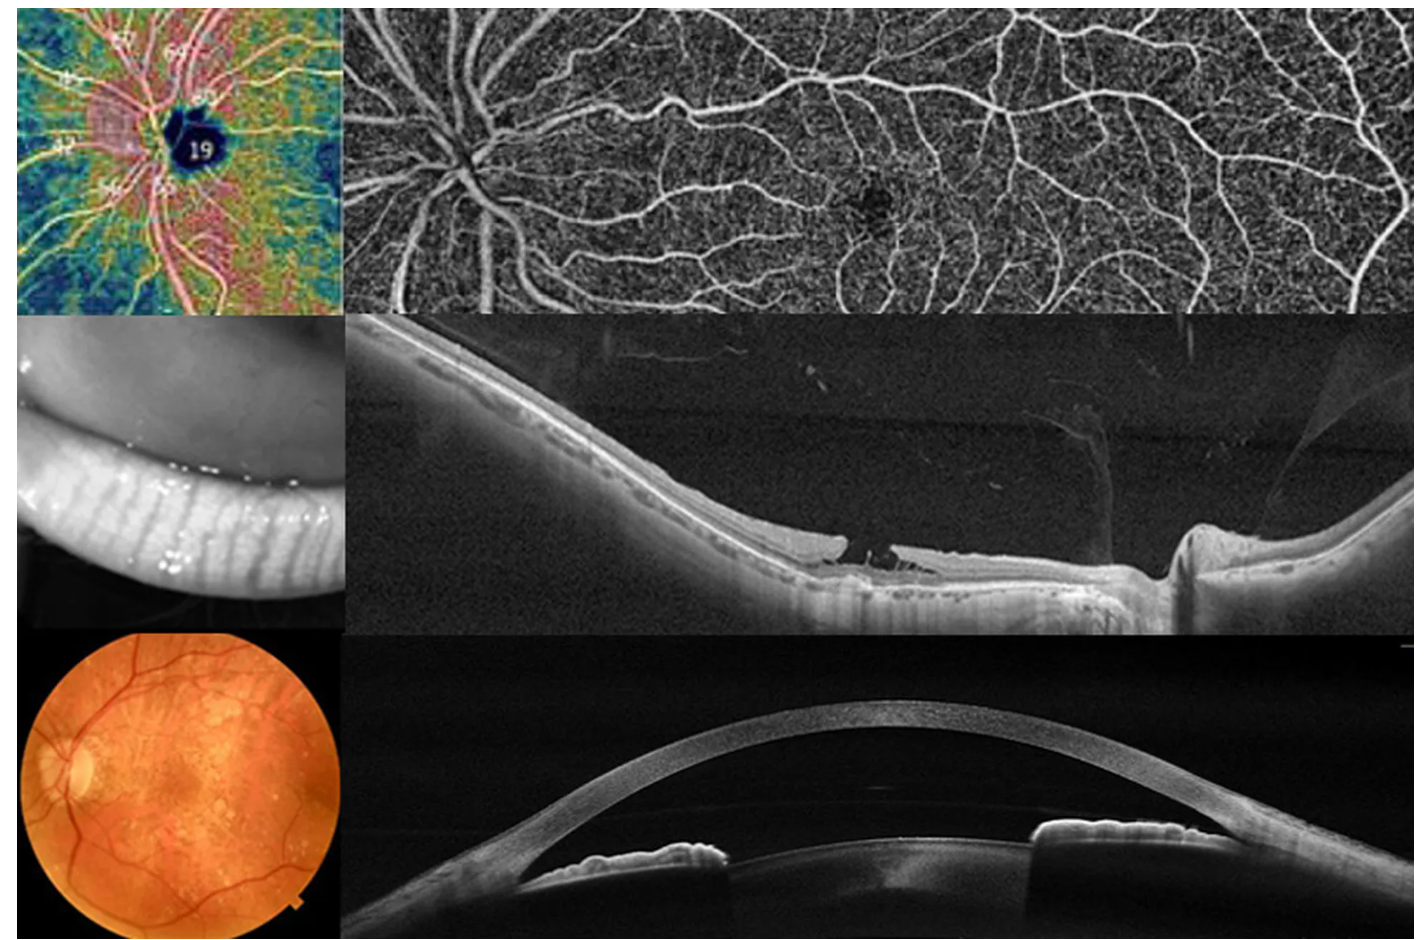

Оптический когерентный томограф Optovue Solix обладает повышенной скоростью сканирования — 120 000 А-сканов в секунду. SOLIX предоставляет множество инструментов для нового поколения борьбы с заболеваниями, которые повышают пропускную способность и обеспечивают превосходный уход за пациентами. В отличие от томографов более ранних поколений ОКТ SOLIX OPTOVUЕ может определять наличие конкрементов и новообразований сосудов сетчатки и хориоидеи, позволяет получать максимально точную послойную визуализацию структур глаза.

- Диапазон сканирования в режиме ангио-ОКТ — от 3х3 до 18х18 мм;

- Размер зоны сканирования в аксиальном направлении — 6,25 мм;

- Программа AngioAnaliticsTM для количественного анализа сосудов сетчатки;

- Полноразмерное сканирование передней камеры;

- Оптическая пахиметрия, картирование эпителия и стромы роговицы в зоне диаметром 10 мм.